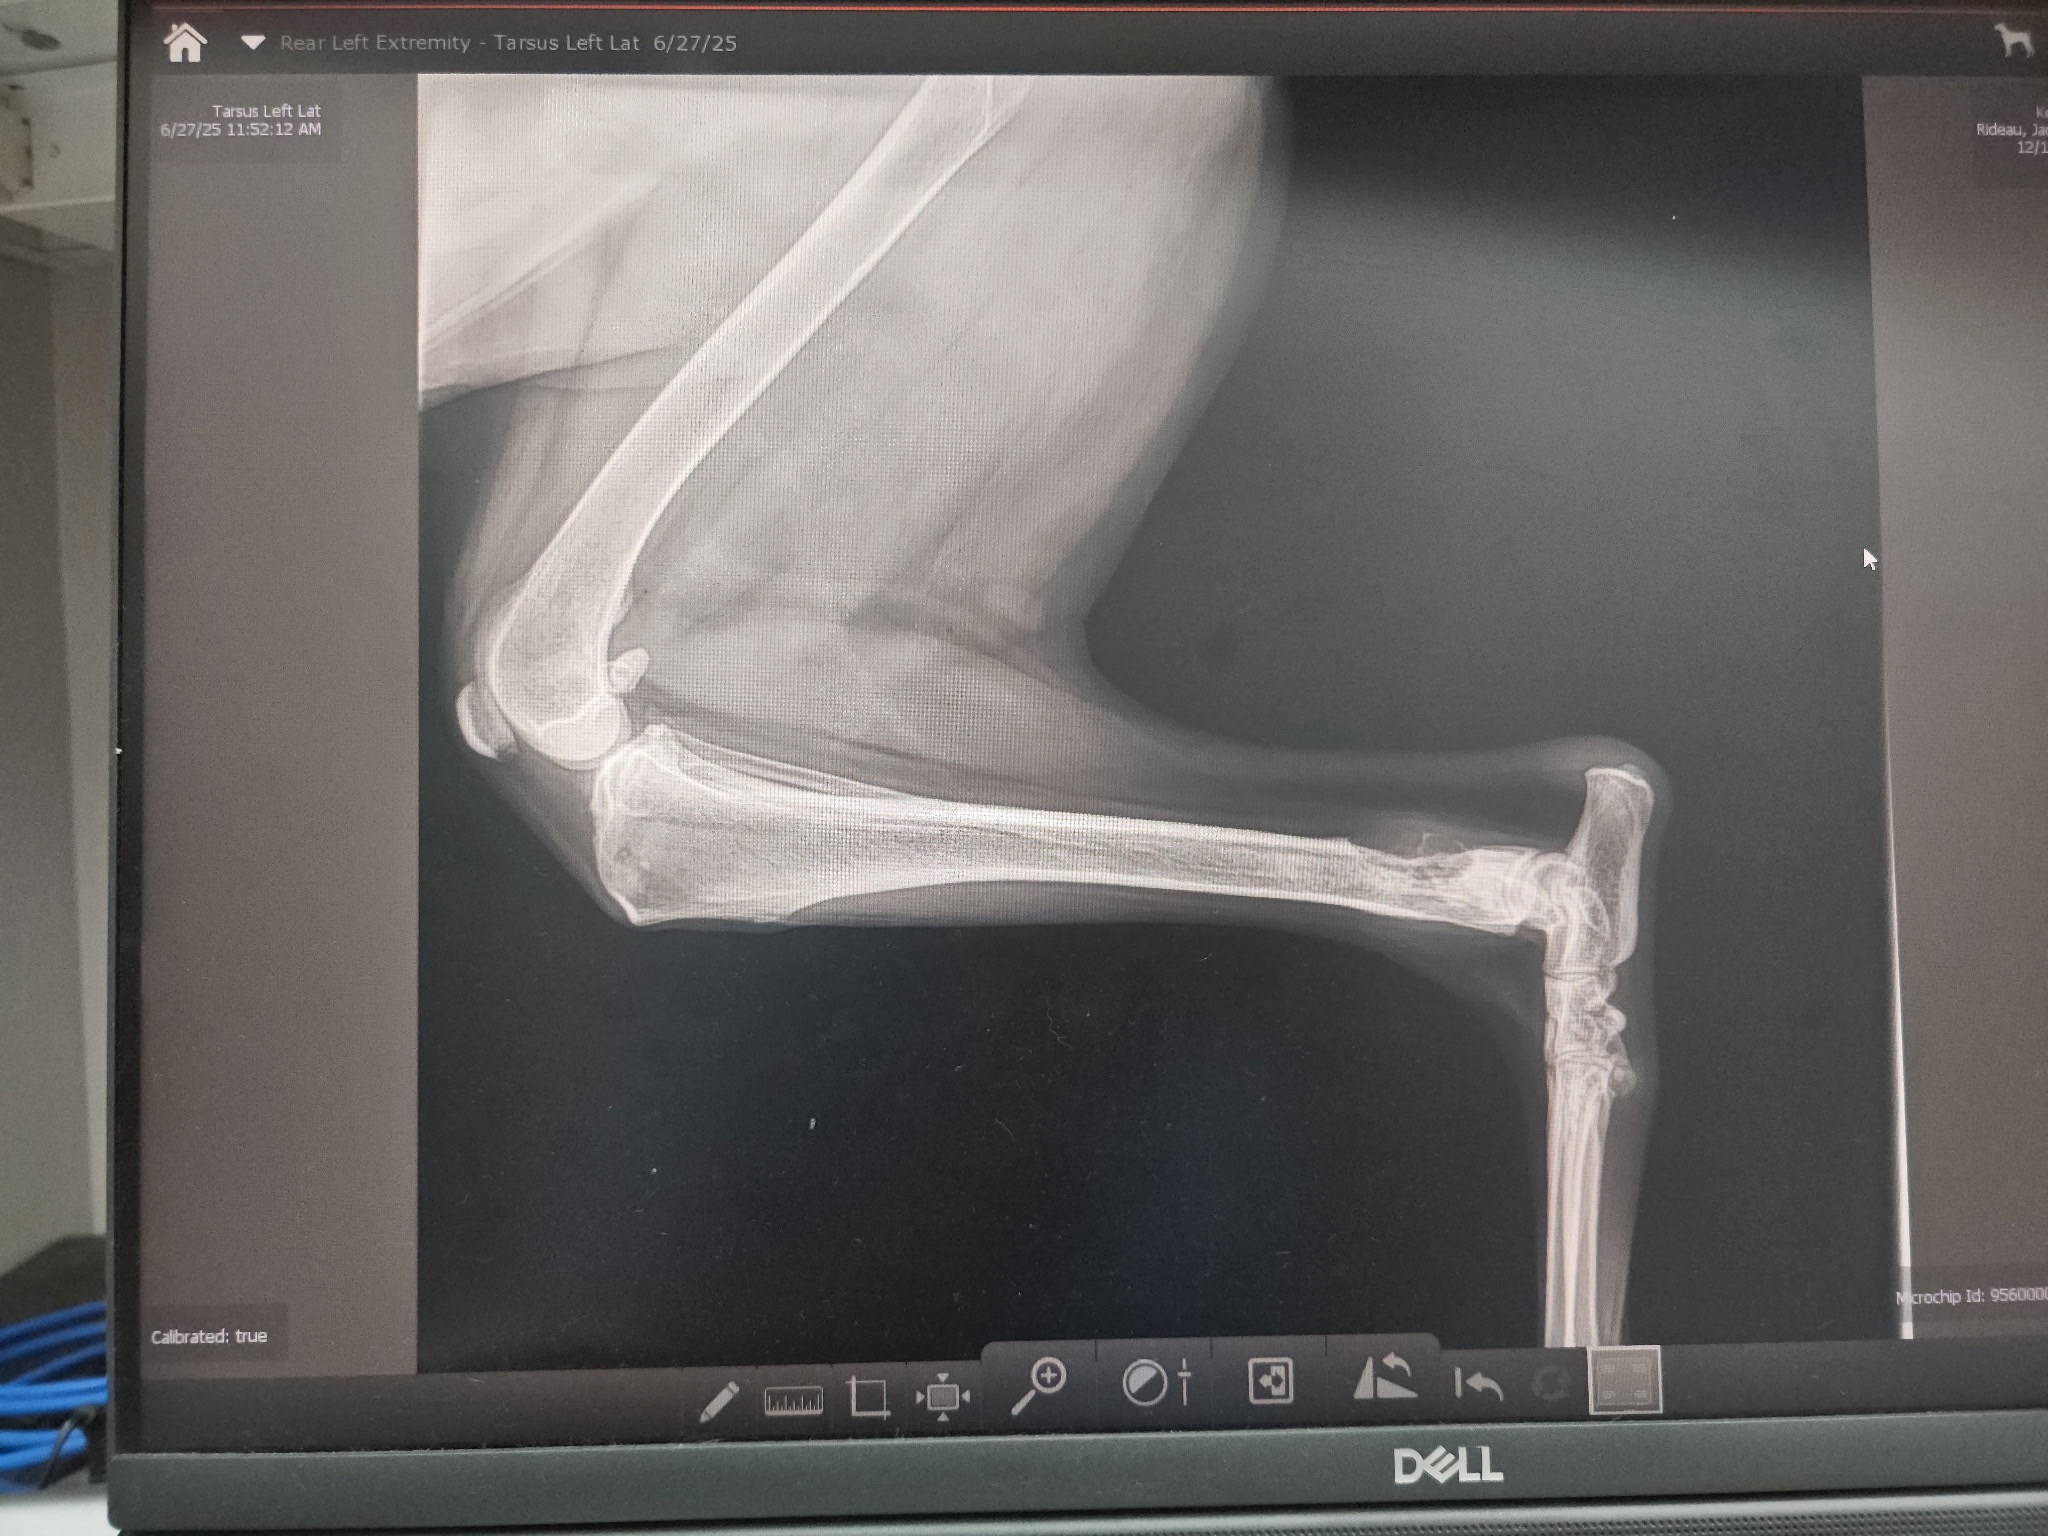

- Hello everyone! This is Kona aka Koney. She is a 10-year-old German Shepherd we have had in our family since the day she was surrendered, found abandoned in a house at only 4 weeks of age. She is a great dog and a part of our family, helping raise our 2 kids their entire lives. Kona has had her medical ailments like any family pet does, but now we need your help. Kona developed a bone mass that we noticed almost immediately about 6 weeks ago that has started eating away at the bone. She is in a lot of pain and has been seen by 3 veterinarians, including being referred to oncology. The treatment now to keep her comfortable and prolong her life is amputation of her rear leg. From there, we test the mass and reassess for further treatments. We are not selfish in choosing to do this vs. euthanizing. Kona has had labs and chest X-rays showing she is otherwise a perfectly healthy dog. It is not her time to go. Even with not being able to use her leg and all the pain she is in, she still brings me her toys to play with just days ago. We are scheduled for surgery this week and will be starting around $7500. From there, we will be beginning physical therapy and possibly chemo treatments depending on what we get as a definitive diagnosis. Our family knows this GoFundMe will not cover everything. We are prepared to be in a hardship ourselves to pay all the costs and are currently applying for grants to help assist. Thank you for reading our story and helping save our Koney.